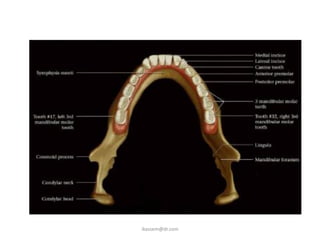

Lower 45° occlusal

This projection is taken to show the lower

anterior teeth and the anterior part of the

mandible. The resultant radiograph resembles

a large bisected angle technique periapical of

this region.